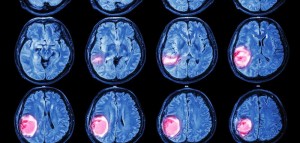

Evolución de un tumor cerebral. Imagen cortesía de brainspinesurgery.

La resonancia magnética encontró que tenía un tumor cerebral, un hemangiopericitoma del tamaño de un huevo en la corteza orbitofrontal derecha, la zona situada en la región más anterior e inferior del hemisferio cerebral derecho, por detrás de la cuenca del ojo derecho.

Finalmente el tumor fue extirpado y tras completar con éxito el programa de rehabilitación contra la adicción al sexo de Sexólicos Anónimos el hombre pudo volver a su hogar. Sin embargo, en octubre de 2001, volvió a quejarse de dolores de cabeza y comenzó de nuevo a recopilar pornografía a escondidas. Un nuevo escáner reveló que el tumor había vuelto a crecer y tras su segunda eliminación quirúrgica, el comportamiento ilegal e inmoral desapareció por segunda vez, reforzando esa relación causal entre el tumor y la pederastia.